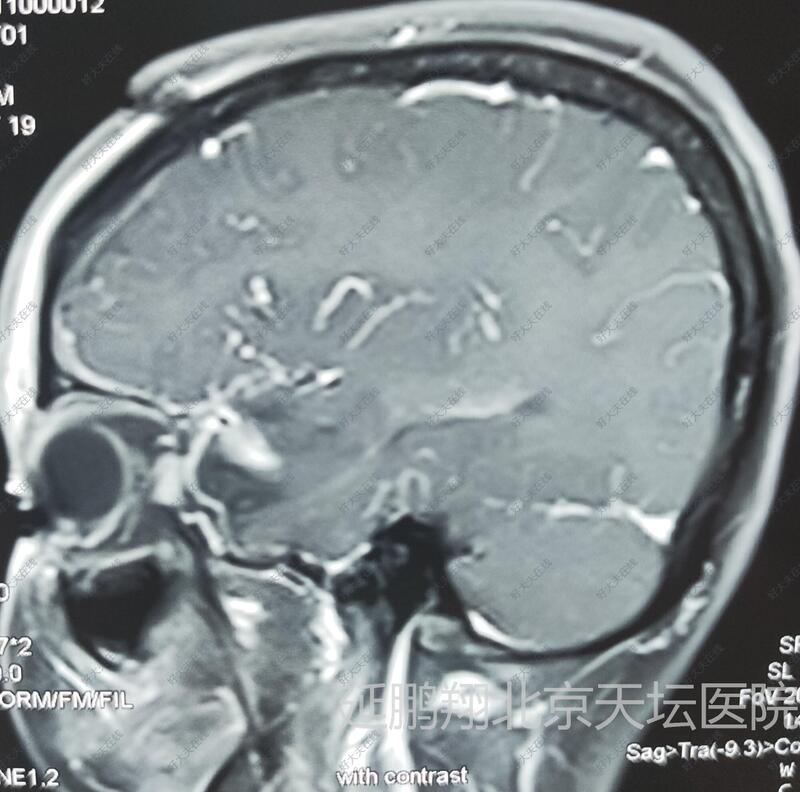

左鞍旁脑膜瘤

女性,48岁。发作性心悸,心烦,头晕11月。CT和MRI显示左侧鞍旁脑膜瘤,与海棉窦及颈内动脉及大脑中动脉关系密切。

术后病人恢复顺利,睡眠,进食,精神状态,行走均正常。常规复查核磁,显示肿瘤消失。